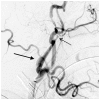

Eagle syndrome is a rare condition resulting from elongation of the temporal styloid process or calcification of its associated stylohyoid ligaments. Although usually presenting with pain or odynophagia, Eagle syndrome has been reported to cause a multitude of neurologic symptoms or vascular complications, some of which can be life-threatening. We present a case in which an endovascularly placed internal carotid artery stent in close proximity to a calcified stylohyoid ligament resulted in stent fracture with subsequent stent and vessel occlusion. We review and discuss the presentation, diagnosis, etiology, complications and treatment options of the syndrome.